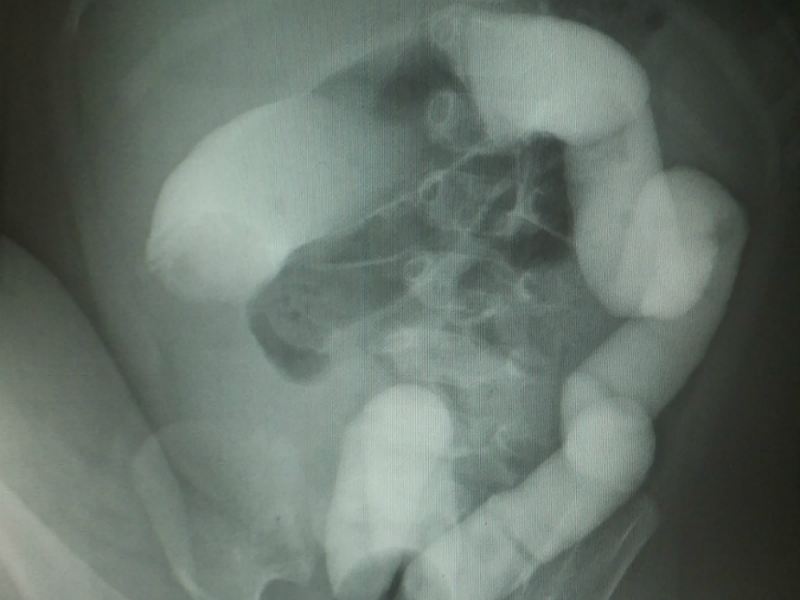

진단은 타겟 사인(target sign)이라고 해서 초음파로 장이 겹쳐져 막힌 부분을 확인하는 것이고 치료는 항문을 통해 공기나 조영 물질을 섞은 액체로 장을 밀어내어 펴주는 치료를 하게 됩니다. 간혹 관장 정복에 실패하거나 장천공이 발생하면 수술적 치료가 필요한 경우도 생깁니다.

021103.png